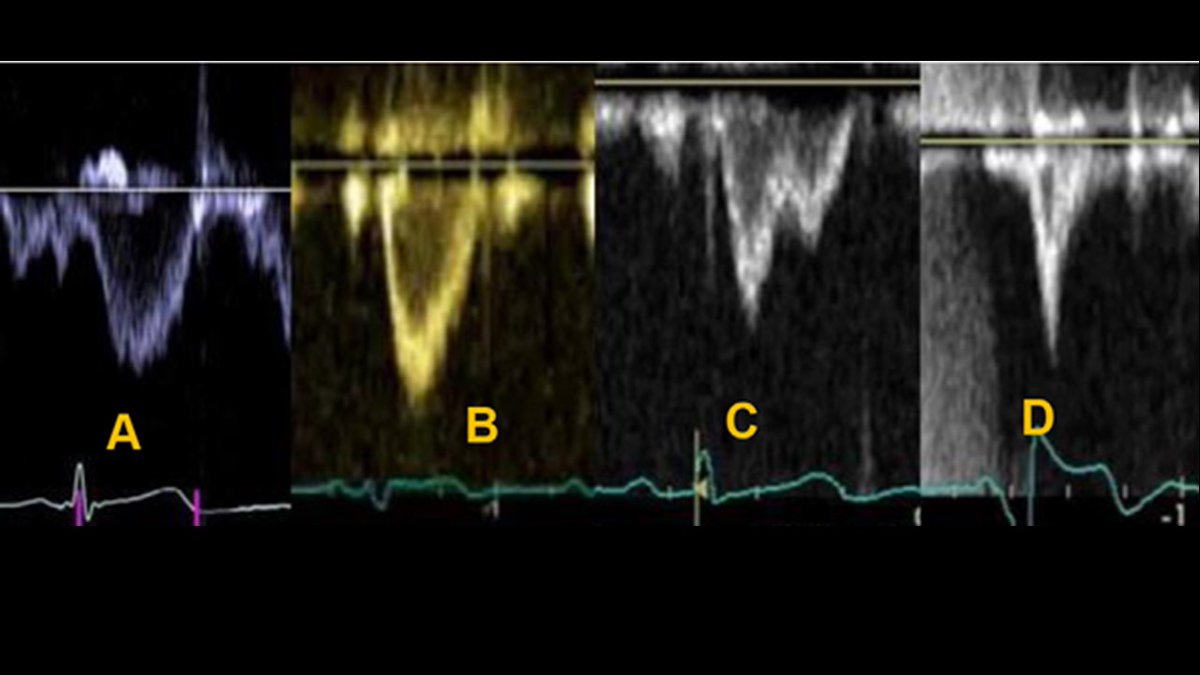

@NadeenFaza @JiwonKimMD @PWesslyMD @ASE360 @purviparwani @iamritu @DavidWienerMD @rajdoc2005 @boegel_kelly @GWhalleyPhD #ASEchoJC In normal subjects, RVOT VTI profile is parabolic, peaking in mid-systole, indicating a highly compliant PV bed with low resistance. As PVR progressively increases > more triangular. Increasing impedance to pulmonary flow can lead to notching in the mid-systolic phase